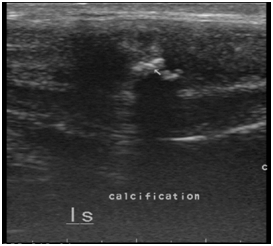

Another 45year old male patient presented with painful erection and palpable nodular lesion in the middle and distal third of penis since last 8-10months to skin and veneral disease department. He was referred to the ultrasound department for sonography of the penis. Local ultrasound of penis done with linear 9-11 MHz probe revealed an echoreflective calcified plaque in intercorporeal septum measuring approximately 8mm in length and 2mm in thickness causing posterior acoustic shadowing (Figure 3).

Figure 3 Radiograph of penis with soft tissue exposure showing multiple calcific plaques in mid penile shaft.